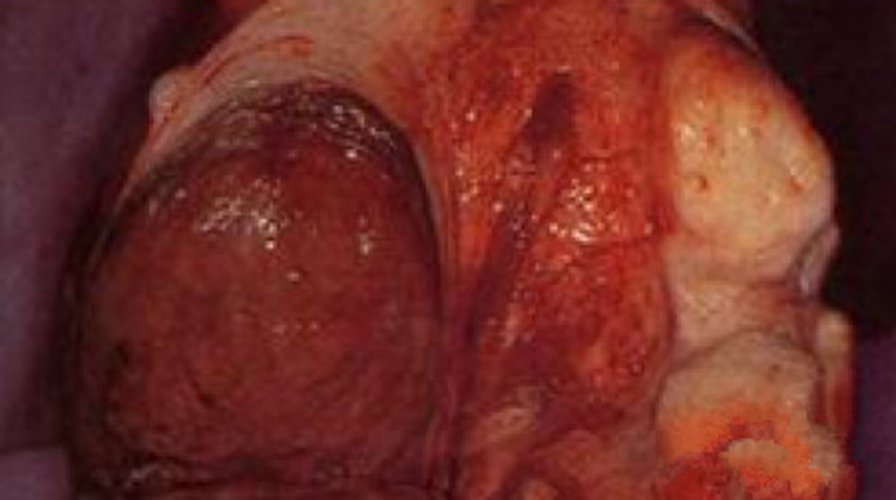

子宫脱垂的子宫去留问题

什么是子宫脱垂你知道吗